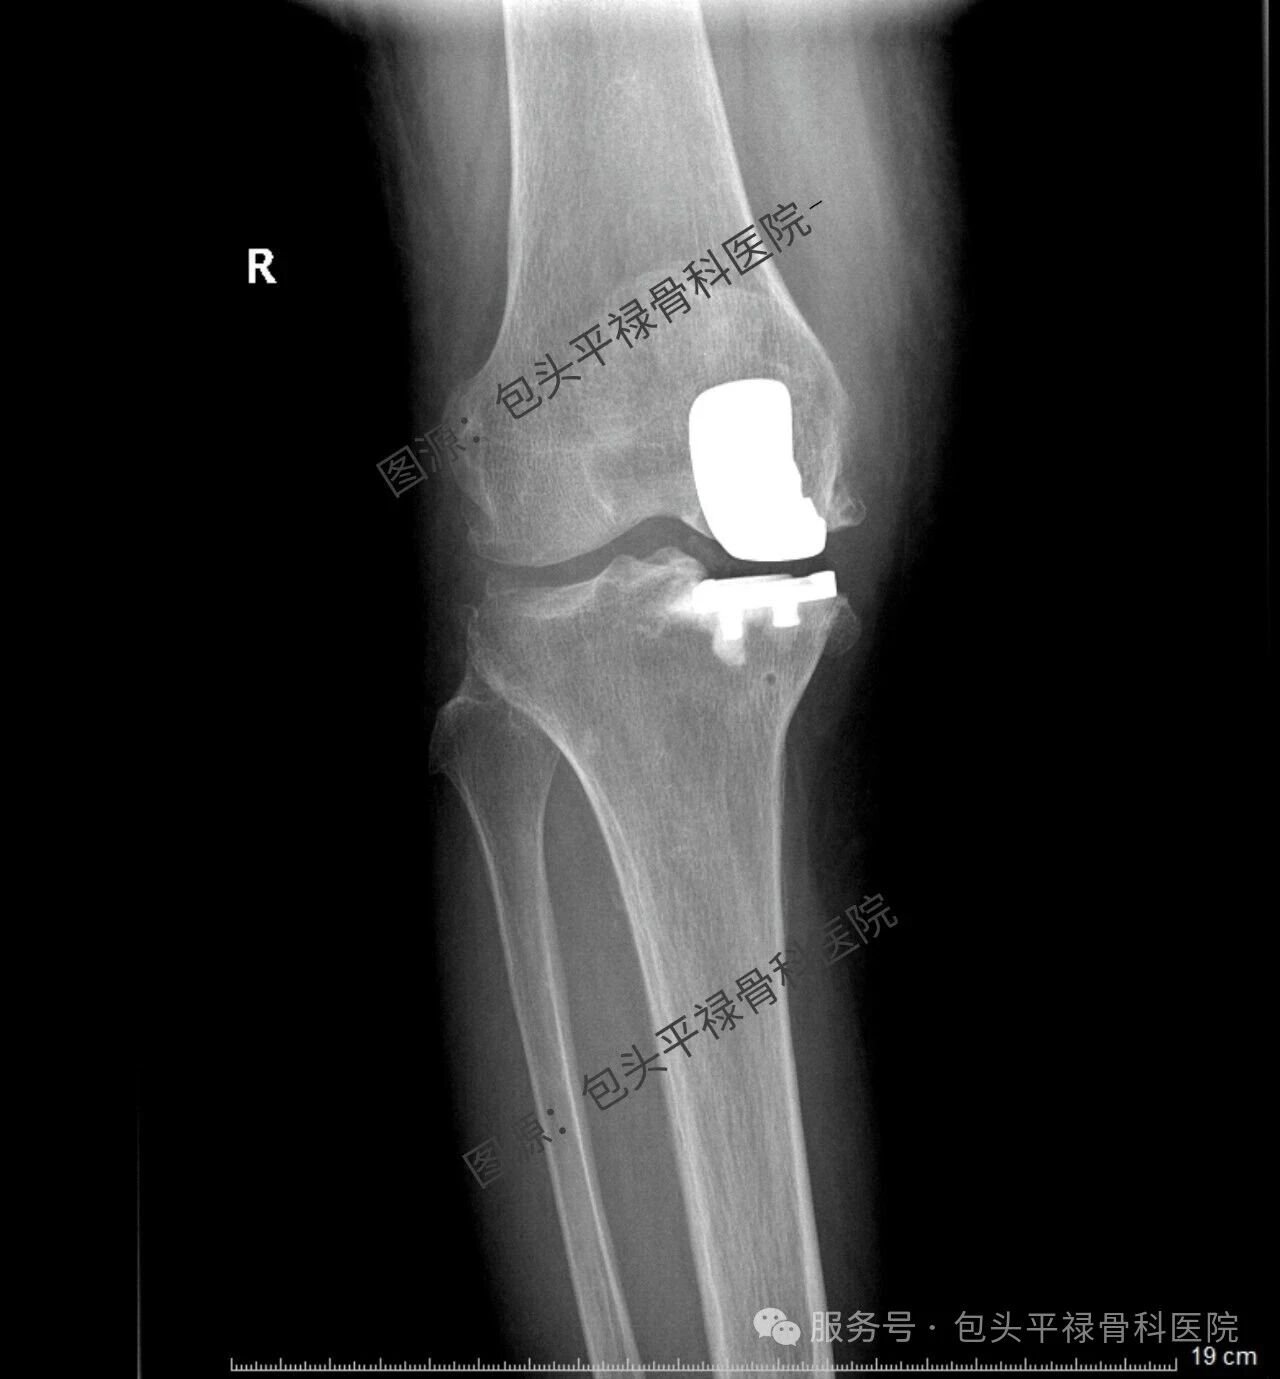

其实,现代医疗技术日趋精准,如果患者的关节炎只局限于膝关节的一个部分(单侧间室),那么TA很可能适合一种更为精准、创伤更小的手术——膝关节单髁置换术。

单髁置换:精准的“局部翻新”

膝关节单髁置换术相当于“局部翻新”,就是只置换“坏掉房间”的磨损表面,仅将受损的软骨和部分骨质去除,替换为人工假体,而完好的软骨、交叉韧带及其他结构都得以最大程度的保留。